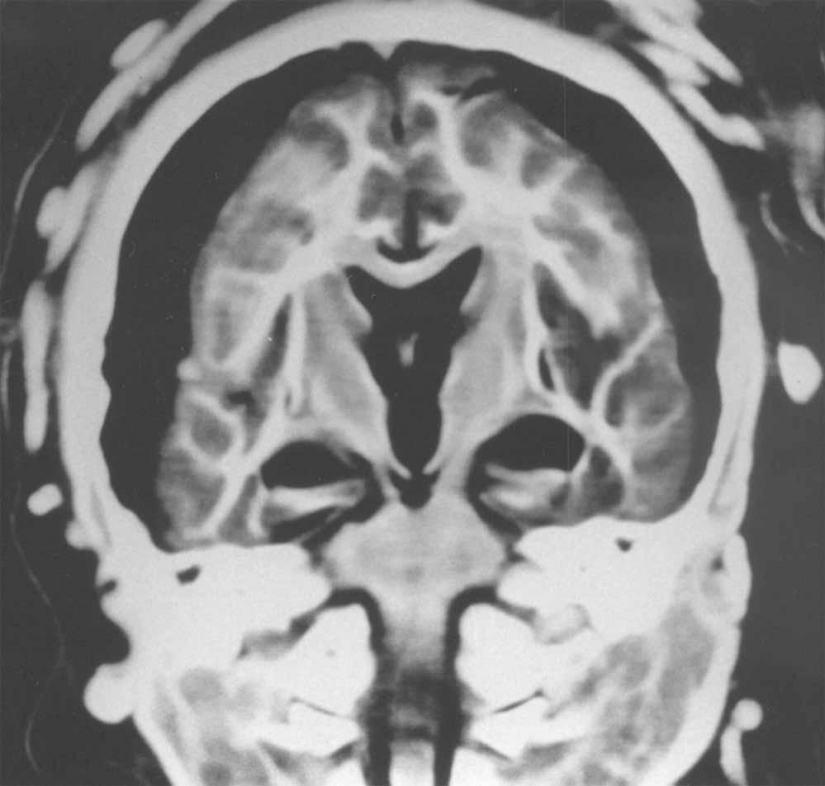

7. Y que los rayos x mostraron que el cerebro de 5 años niño se quedó en perfecto estado.